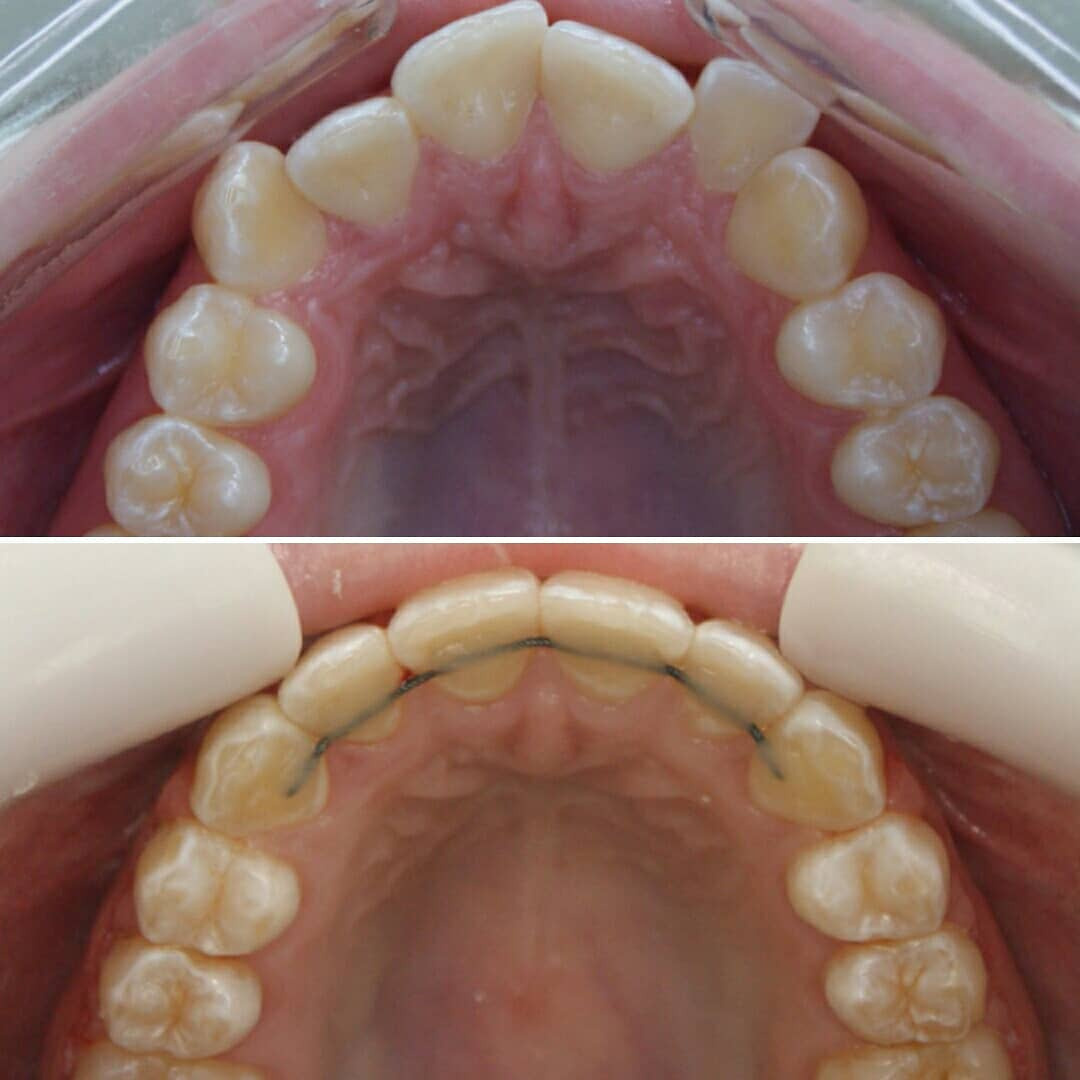

Как должно быть:

1) Широкие промежутки между всеми молочным зубами говорят о хорошем росте челюстей, о том, что запас места для постоянных зубов есть.

2) Наклоны зубов прямые, зубы не вдавлены внутрь, как на первой фотографии. Правильный наклон обеспечивается правильным положением языка и хорошим жеванием.

3) Бугры клыков и боковых зубов, а также режущие края передних зубов должны стираться. Если зубы острые, значит ребёнок не жуёт. Острые бугры блокируют плавные движения челюсти и ограничивают рост. Надеюсь, понятно. ПРОВЕРЯЙТЕ!